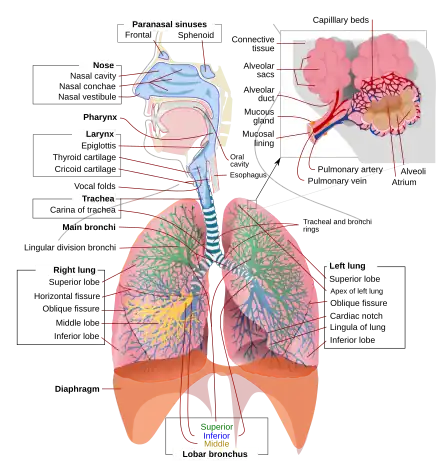

Schematic view of the human respiratory system with their parts and functions. | |